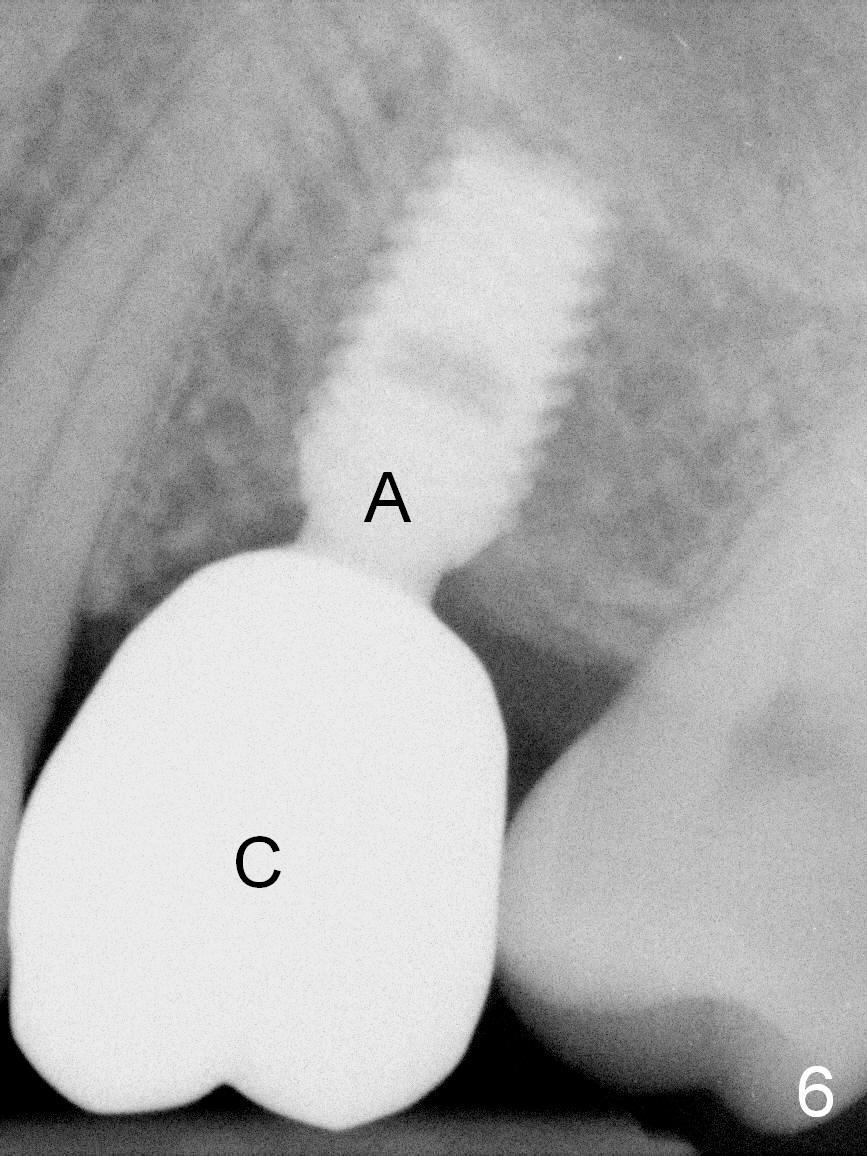

A 49-year-old man is an engineer. The tooth #14 is missing (Fig.1,2). He wonders how a one-rooted implant can replace a three-rooted tooth. Anyway, osteotomy is initiated at the site with 2.5 mm reamer in place (Fig.3). A 5x8 mm Bicon implant is placed (Fig.4). Seven and a half months later, the bone density next to the implant plateau appears to increase (Fig.5 arrowheads, as compared to Fig.4). The beauty of Bicon implant is that the crown (Fig.6 C) can be extraorally cemented to the abutment (A) prior to re-seating. Two years and 3 months post cementation, while no residual cement is visible, the bone density at the crest has increased (Fig.7 arrowheads). The crown is de-cemented 4 years 4 months post cementation; it appears that the abutment is small and short (5x2 mm 10 degree stealth). The bone density of the cortex around the implant (Fig.9 ^) is higher than that at #15 and #3.